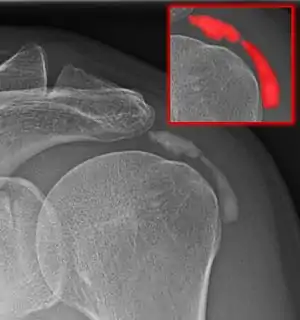

Calcific bursitis refers to calcium deposits within the bursae. This most occurs in the shoulder area. The most common bursa for calcific bursitis to occur is the subacromial bursa. A bursa is a small, fluid-filled sac that reduces friction, and facilitates movements between its adjacent tissues (i.e., between tendon and bone, two muscles or skin and bone). Inflammation of the bursae is called bursitis.

Diagnosis